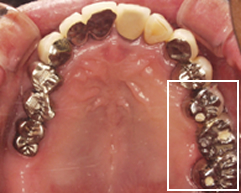

しかし、もうこれ以上歯を削りたくないというご希望があり、インプラント治療を希望される。しかし、インプラントを入れるには前後に十分な隙間がないため吉本歯科医院では、インプラントを入れる為に、二箇所の隙間を一箇所に集める部分的な矯正を行い、インプラントが入るスペースを作ってからインプラント治療を行う。

抜けている所にインプラントを入れる為部分的な矯正を行い、隙間を一箇所にまとめインプラントが入るスペースを作ります

治療前の上の歯

↓

治療後の上の歯

インプラントを埋入後、かみ合わせ部分には金属を使用。

一番奥の歯を金属とし、支えをつけた